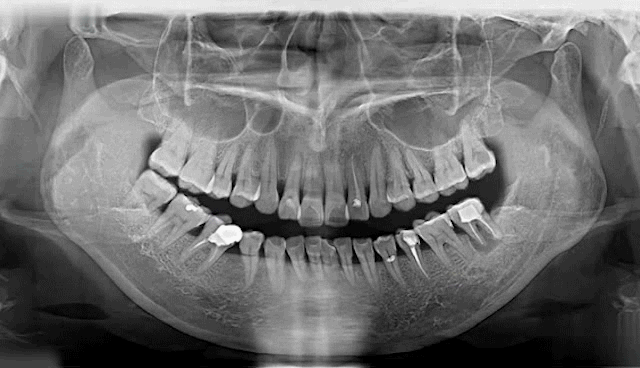

據(jù)醫(yī)學(xué)調(diào)查統(tǒng)計(jì)

我國(guó)35歲以上人群中

逾88%的人存在蛀牙等口腔問(wèn)題

65歲以上的老年人群中

平均缺牙數(shù)量超過(guò)11顆

蛀牙率近98.4%,而調(diào)節(jié)率僅1.9%左右

▲Deepcare AI分析模擬未來(lái)10年口腔變化情況

牙齒脫落是由齲齒、牙周病等口腔問(wèn)題導(dǎo)致的,不是單純的老化現(xiàn)象。牙齒健康至關(guān)重大,所謂“缺牙一顆,全口遭殃”,牙齒缺失一顆會(huì)引起鄰牙松動(dòng)、對(duì)牙伸長(zhǎng)、引發(fā)牙周病,終導(dǎo)致余牙逐漸脫落等一系列問(wèn)題,還會(huì)因咬合紊亂致使面容蒼老、咀嚼功能變差引發(fā)腸胃疾病,嚴(yán)重影響身體健康。